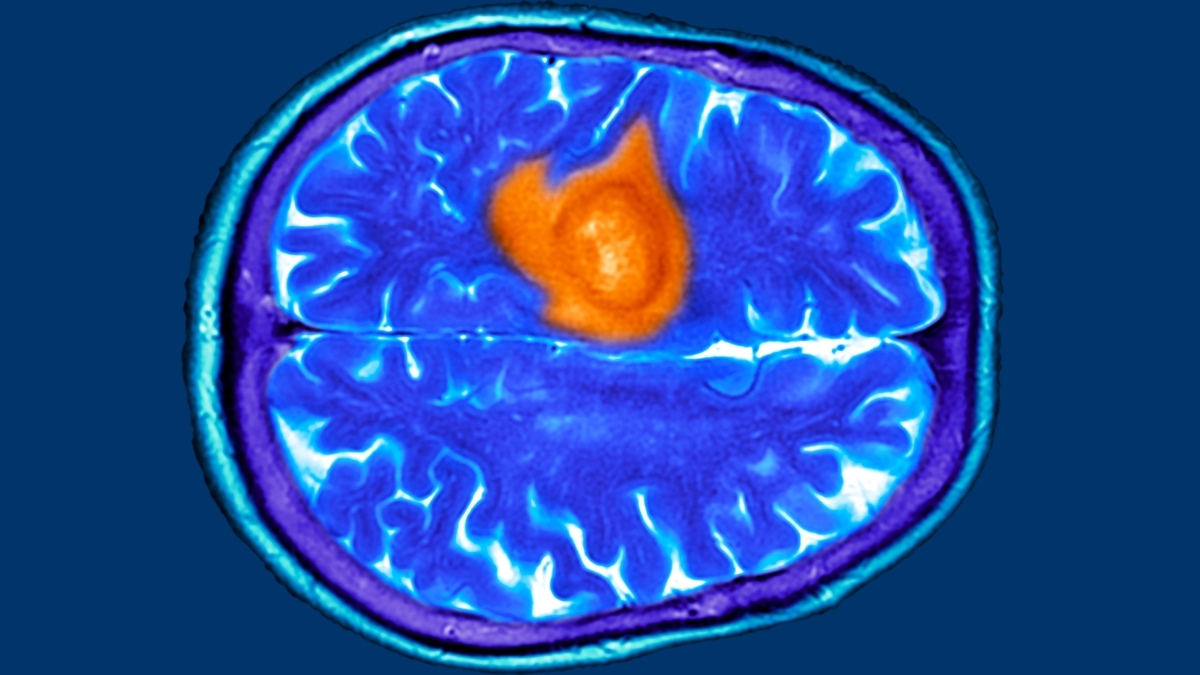

Αυτά είναι τα 7 προειδοποιητικά σημάδια καρκίνου του εγκεφάλου!

Σύμφωνα με την Laura Standen, διδακτορική ερευνήτρια στο Ινστιτούτο Wolfson σε άρθρο που δημοσιεύει αναφέρεται στα 7 προειδοποιητικά σημάδια του καρκίνου του εγκεφάλου. Όπως σημειώνει η ίδια ως μέρος της έρευνάς της, την οποία μπορείτε να βρείτε εδώ, με όσους ασθενείς έχει μιλήσει κατά τη διάρκεια της ακαδημαϊκής της καριέρας, όλοι της ανέφεραν ένα κοινό […]